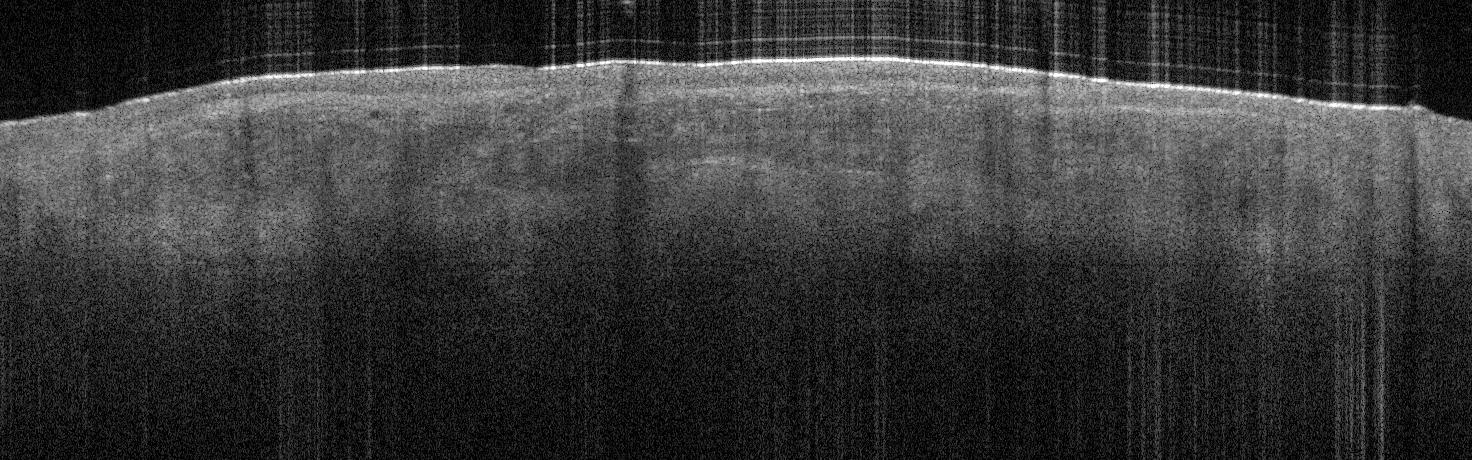

VA33: Superior Nasal Ala, Bilateral, Normal